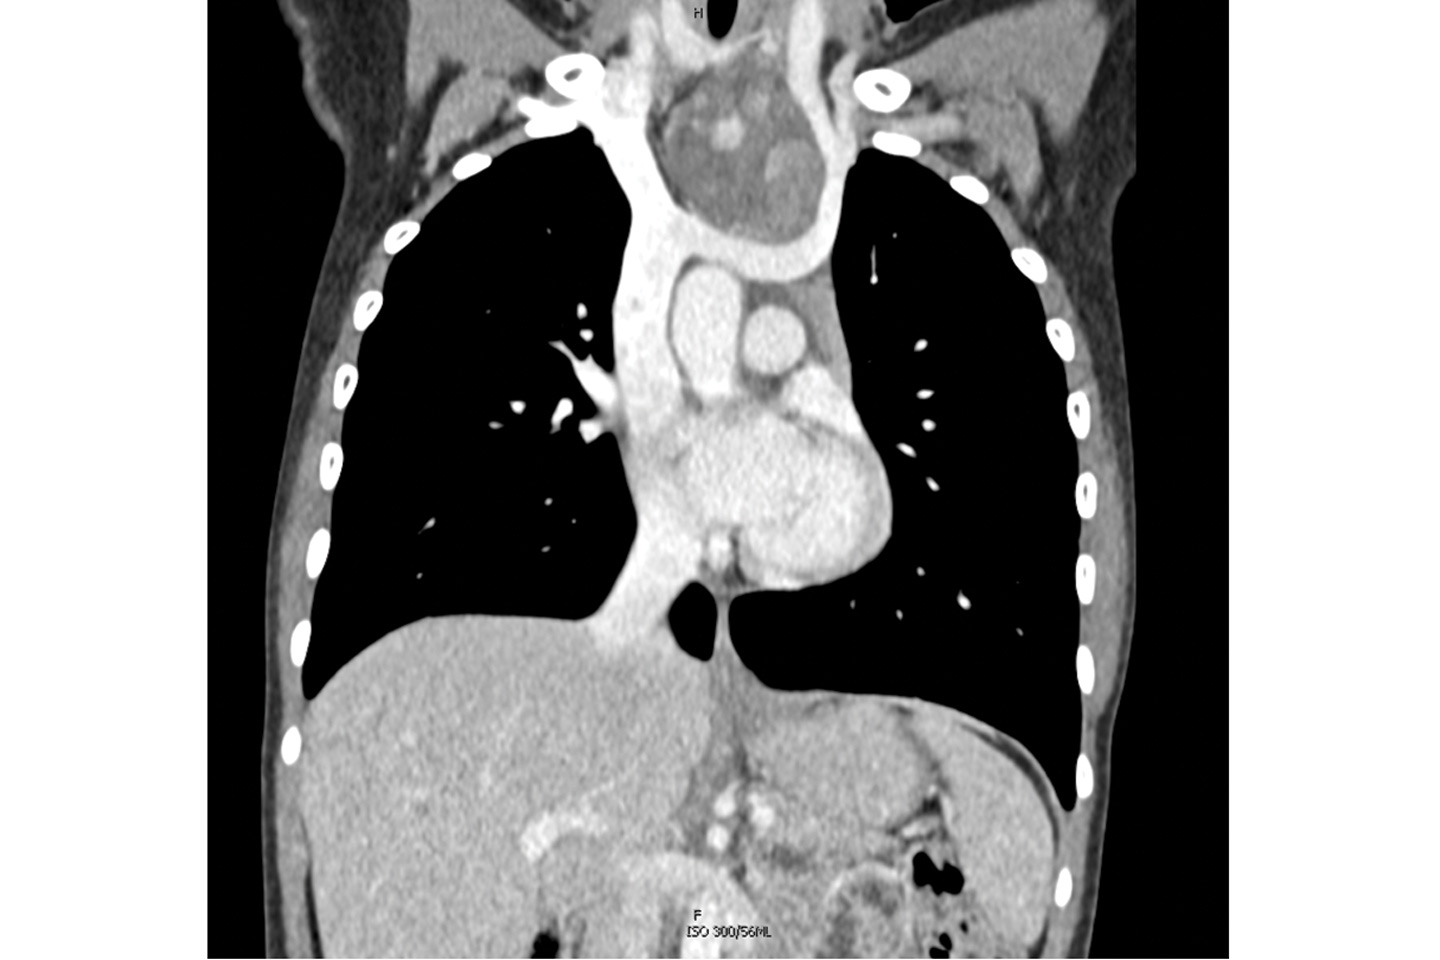

Preoperative CT scan of the patient’s chest showing the mediastinal tumor. Source: NYU Langone Health.

1 of 5